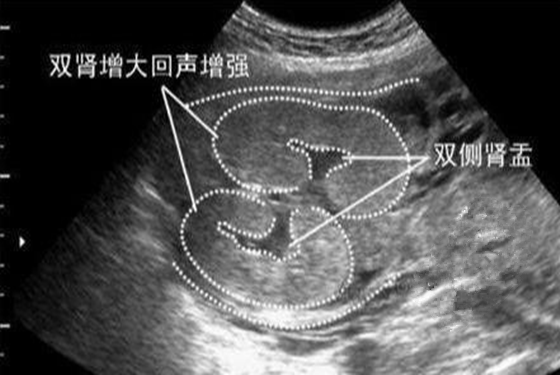

5、B超单上肾盂分离看男女,说是肾盂分离的大多为男孩,肾盂没有分离的大多为女孩。其实,胎儿肾盂不分离的为正常现象,肾盂健康的情况,可能是胎儿憋尿,或者尿道狭窄、堵塞引起的结果,与胎儿性别并无太大的关系,所以,大多数网友表示,这种说法也是不靠谱的。